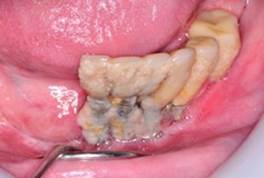

Early: Probing depth >4 mm, with bleeding and/or suppuration in >2 implant sites, and bone loss <25% of the total implant length (Fig. 2)

Moderate: Probing depth >6 mm, with bleeding and/or suppuration in >2 implant sites, and bone loss between 25% and 50% of the total implant length (Fig. 3)

Advanced: Probing depth >8 mm, with bleeding and/or suppuration in >2 implant sites, and bone loss >50% of the total implant length (Fig. 4)